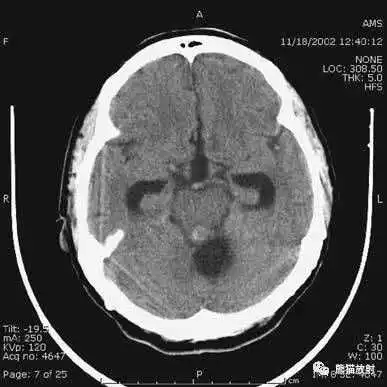

▲

动脉瘤破裂导致蛛网膜下腔出血、

脑室积血、非交通性脑积水。

与外伤性蛛网膜下腔出血不同,动脉瘤破裂导致的SAH常不累及大脑凸面,而位于基底池附近。脑动脉瘤常位于鞍上池的Willis环血管。

A:四脑室积血;

B:中脑导水管、环池、右侧侧脑室颞角积血,前交通动脉处(动脉瘤好发位置)出血密度较高;

C:三脑室积血;

D-F:侧脑室积血,蛛网膜下腔出血(血液代替了脑脊液)。